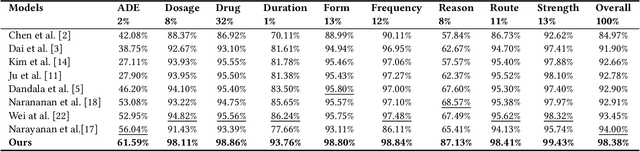

Extracting meaningful drug-related information chunks, such as adverse drug events (ADE), is crucial for preventing morbidity and saving many lives. Most ADEs are reported via an unstructured conversation with the medical context, so applying a general entity recognition approach is not sufficient enough. In this paper, we propose a new multi-aspect cross-integration framework for drug entity/event detection by capturing and aligning different context/language/knowledge properties from drug-related documents. We first construct multi-aspect encoders to describe semantic, syntactic, and medical document contextual information by conducting those slot tagging tasks, main drug entity/event detection, part-of-speech tagging, and general medical named entity recognition. Then, each encoder conducts cross-integration with other contextual information in three ways: the key-value cross, attention cross, and feedforward cross, so the multi-encoders are integrated in depth. Our model outperforms all SOTA on two widely used tasks, flat entity detection and discontinuous event extraction.